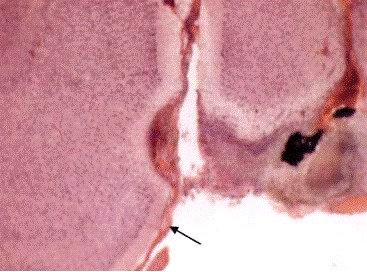

Сопоставление внешних (неврологических и двигательных) эффектов повреждения с результатами морфологического контроля свидетельствуют об определенном соответствии между локализацией и степенью электролитического разрушения мозга, а также характером послеоперационных нарушений.

Так, морфологические исследования не выявили точного попадания коагулирующего электрода в левое вестибулярное ядро Дейтерса в первой группе ни у одной крысы. У животных подгруппы Б, с быстро регрессировавшими послеоперационными неврологическими нарушениями, в двух случаях очаг повреждения захватывал область моторного ядра лицевого нерва и гигантоклеточного ретикулярного ядра; еще в одном наблюдении этот очаг не был обнаружен вовсе. В подгруппе А, у крыс, с отсутствовавшими после операции видимыми изменениям позы и двигательной активности, в 5 случаях имело место попадание коагулирующего электрода в область вентрального и дорсального кохлеарного ядер (рис. 3.5,Б,2), в одном - в левую ножку мозжечка. У одной крысы очаг разрушения не определялся.

Во второй, «осложненной», группе у 8 из 9 крыс обнаружено точное попадание коагулирующего электрода в левое вестибулярное ядро Дейтерса. У одной крысы морфоконтроль не проводился. При этом объем и характер разрушения варьировал у разных животных. Отмечены случаи локального (рис. 3.5,Б,1) и довольно обширного разрушения вестибулярного ядра с большой протяженностью в рострокаудальном направлении (рис. 3.5,Б,3). У двух животных наблюдалось полное замещение области разрушения глиальным рубцом. Важным представляется тот факт, что течение послеоперационного периода по неврологическим показателям не зависело только от объема стволового разрушения. Так, у животного с самым обширным повреждением ядра Дейтерса (рис. 3.5,Б,3) обнаружена достаточно быстрая (через полторы недели) и полная компенсация нарушенных функций. Такими же были сроки редукции неврологических отклонений и в ряде наблюдений с ограниченными разрушениями. В то же время у некоторых крыс с аналогичным или даже меньшим объемом повреждения (рис. 3.5,Б,1) отмечались грубые, не компенсируемые в течение полутора месяцев, поведенческие нарушения. Судя по всему, последствия локального стволового повреждения определяются многими факторами, к числу которых относятся реакция ткани и сосудов мозга на электротравму, целостные церебральные реакции на повреждение и др.

Из семи крыс, погибших во время или в разные сроки после операции, патоморфологические исследования удалось провести лишь в двух случаях. Если в одном из них имело место довольно грубое повреждение ядра Дейтерса, то во втором точное локальное попадание коагулирующего электрода в левое ядро Дейтерса сопровождалось сравнительно небольшим объемом разрушения (рис.3.5,Б,2).

Сходство особенностей гистологической картины повреждения у этого животного и животных из второй группы является еще одним подтверждением нашего вывода о том, что тяжесть послеоперационного состояния не сводится только к локализации и объему разрушения, но определяется, по-видимому, вторичными дисгемическими нарушениями и особенностями протекания системных адаптивно-компенсаторных процессов, которые обусловлены, в частности, индивидуальными особенностями ЦНС.

Рис.3.5. Фронтальные срезы мозга крыс при стволовом повреждении: 1 -вариант с локальным разрушением ВЯД; 2 - повреждение ствола с деструкцией кохлеарных ядер; 3 - обширное разрушение ствола на этом же уровне (показано стрелками)